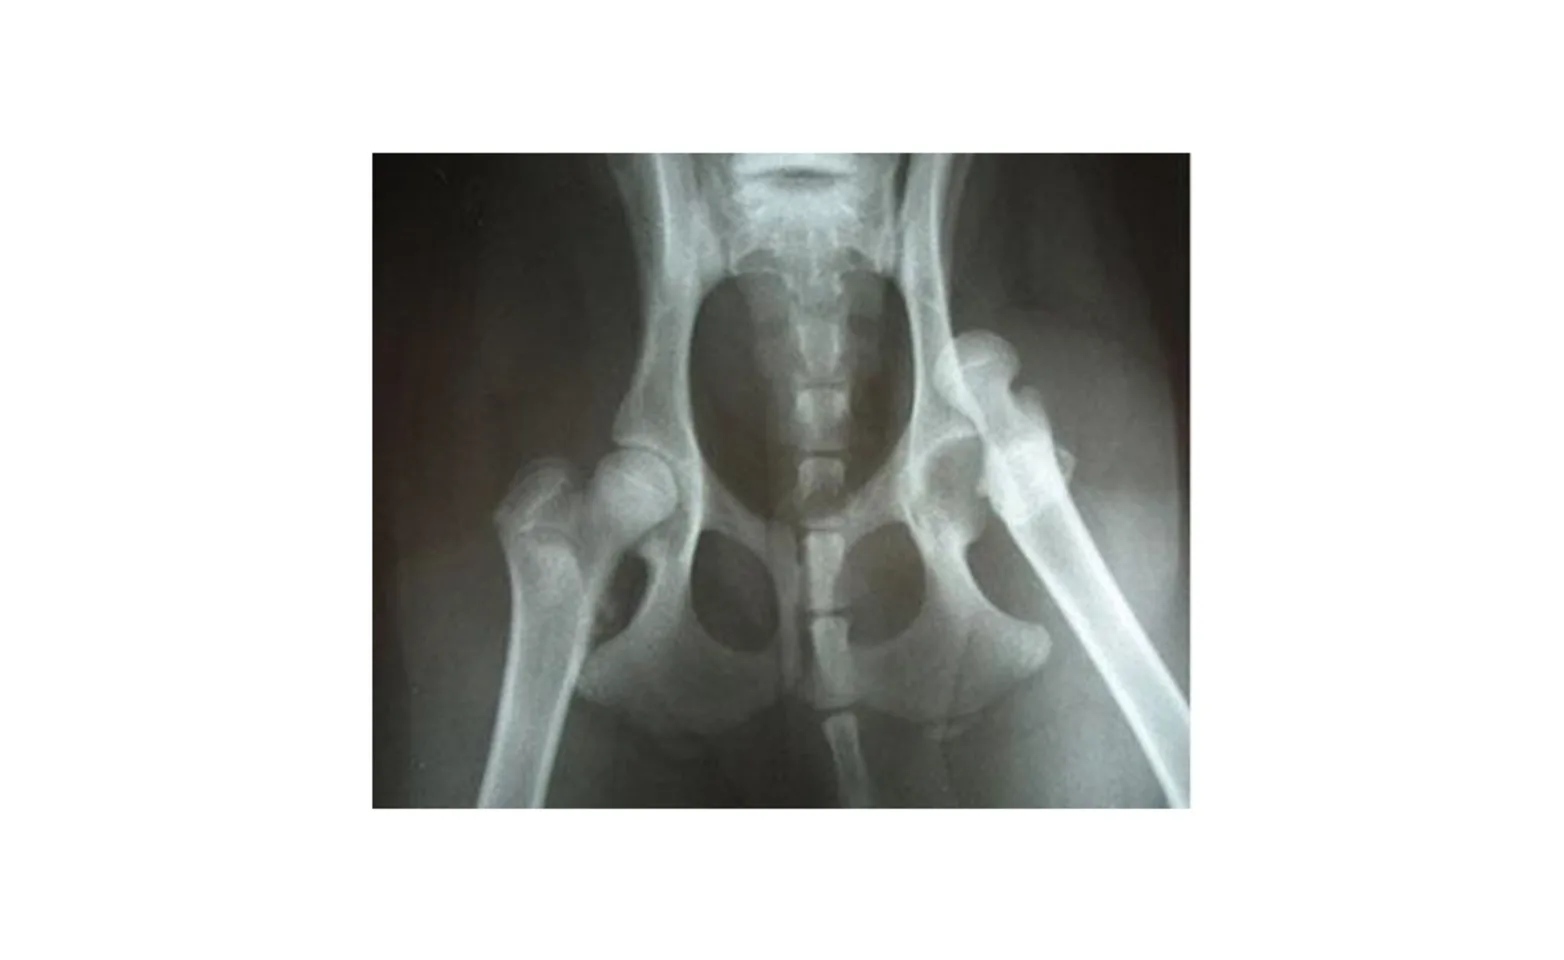

Diagnosis of a hip luxation is made through appearance of the limb, physical exam, and hip radiographs (X-rays). Radiographs of the hip are also important to rule out other conditions such as pelvic fractures, femoral fractures, and/or hip disease. Below is a radiograph of a craniodorsal hip luxation. The left side is a hip in the normal position.